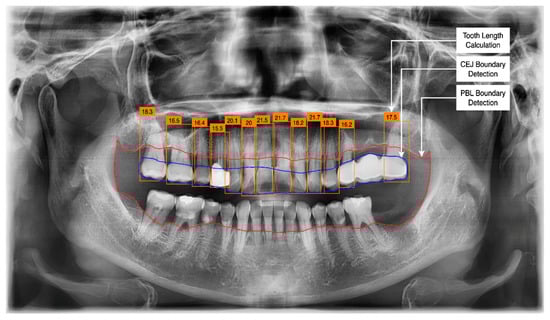

3.2. PBL and CEJ Boundary Detection through U-Net

3.3. Tooth Identification through YOLOv5

3.4. Determination of Tooth Stage through U-Net and YOLOv5 Integration